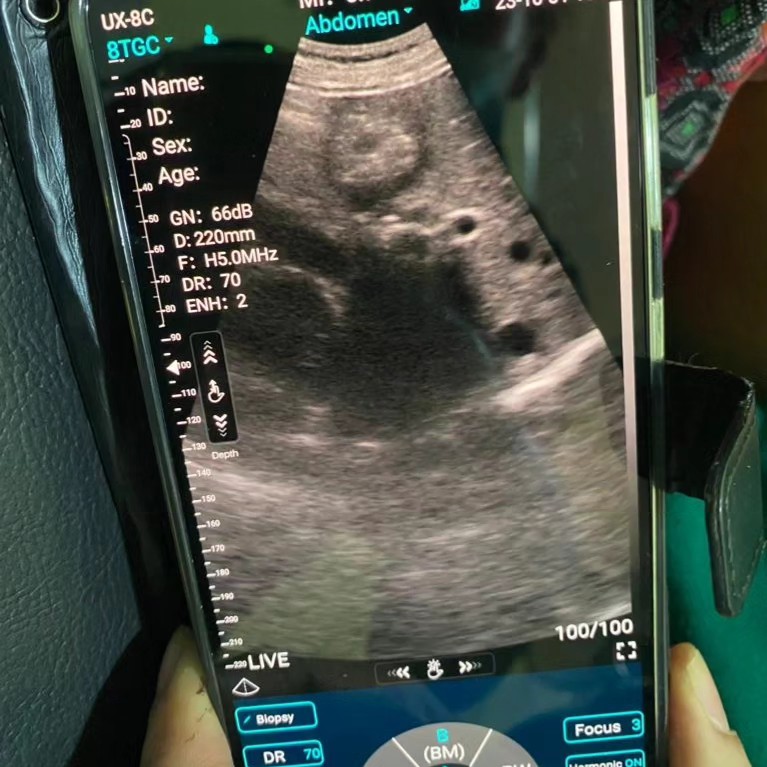

Among the patients seen one particular case stood out—a lady diagnosed with gallstones using ultrasound technology. It's moments like these that underscore the importance of having access to medical care, even in remote areas.

The TrekMedic also encountered challenging cases, like a lady with epigastric pain, unexplained weight loss, night sweats, and a liver lesion. The medical team, including Dr. Jon, diligently worked to provide a diagnosis and appropriate care.